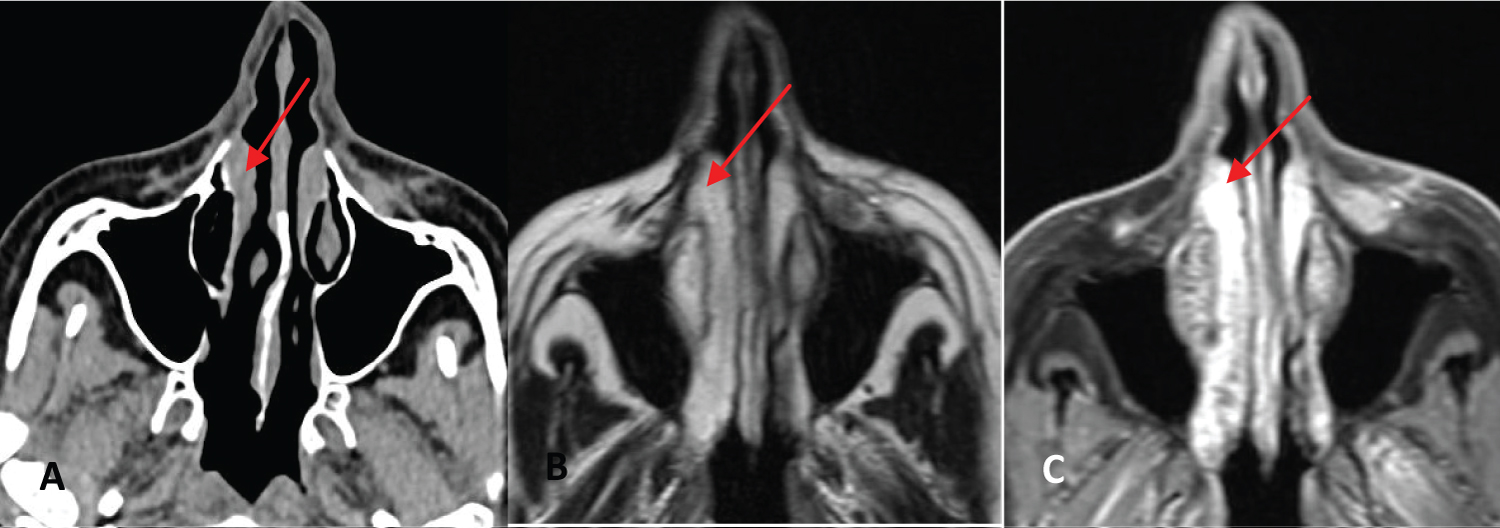

Nasal endoscopy was normal and Computed Tomography (CT) and Magnetic Resonance Imaging (MRI) revealed a subcutaneous tumor without skin infiltration, 8mm in diameter with post-contrast enhancement. It was located at the emergence of the infraorbital nerve from the maxillary sinus (Figure 1).

Figure 1: A: CT where a nodular lesion is observed adjacent to the emergence of the infraorbital nerve, B y C: Axial MRI in T1 and T2 showing a subcutaneous tumor without skin infiltration at the emergence of the infraorbital nerve (red arrows).